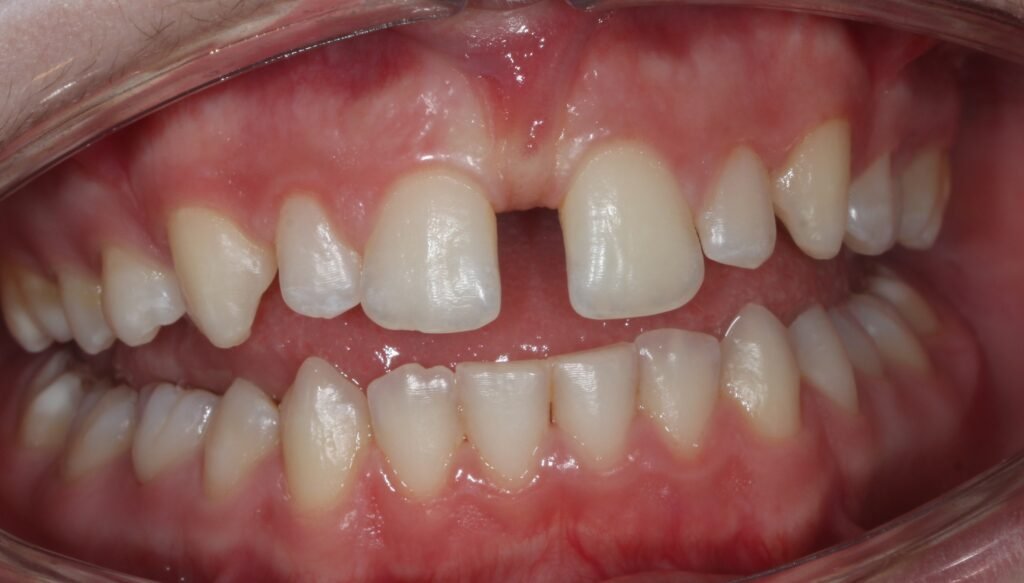

Extracción de Cordales

(Muelas del Juicio)

Las muelas del juicio, o cordales, suelen causar problemas de espacio o infecciones cuando no erupcionan correctamente. Las principales causas de extracción incluyen:

- Pericoronaritis: Es una infección o inflamación de los tejidos que rodean la muela del juicio, generalmente causada por la dificultad de la muela para erupcionar completamente, lo que facilita la acumulación de bacterias.

- Daño dental: Las muelas del juicio pueden dañar los dientes vecinos si crecen de forma incorrecta o se desplazan, lo que puede generar caries o problemas de alineación dental.

- Problemas articulares: La erupción de las muelas del juicio puede generar tensión y dolor en la articulación temporomandibular (ATM) debido a interferencias y prematuridades en la oclusión, provocando molestias o problemas funcionales en la mandíbula.

Realizamos extracciones quirúrgicas de cordales con técnicas que minimizan el dolor y aceleran la recuperación, asegurando una intervención rápida y segura.